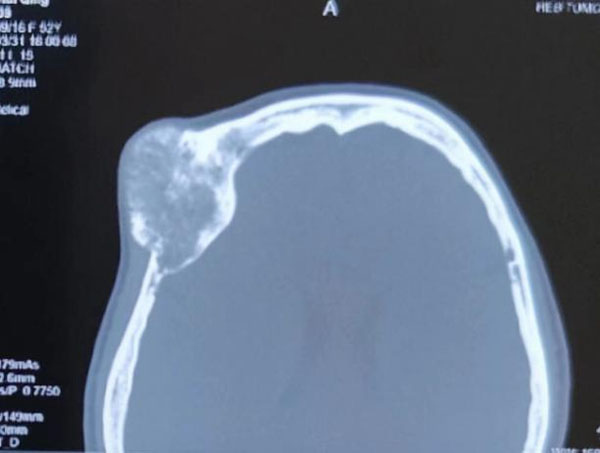

患者主因右眼視物不清伴眼球突出3年,以右眼眶內占位收入我院眼科。眼科郝玉華教授在檢查中發現,患者右眼視力極低,右眼上瞼下垂,眼球突出且運動明顯受限。眼眶CT提示眶內巨大占位,幾乎占據球后整個眶間隙。同側額部顱骨骨質亦顯示巨大腫瘤,約7*7 cm大小。患者已經有上瞼下垂和視力明顯下降的癥狀,表明腫物已經對眶上裂神經和視神經有一定壓迫。